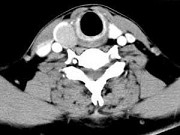

- 单项选择题男,43岁, 右颈部扪及一包块,CT如图所示, 最可能的诊断是 ( )

A、甲状腺腺瘤

B、甲状腺腺癌

C、结节性甲状腺肿

D、甲状腺原发淋巴瘤

E、甲状腺转移瘤